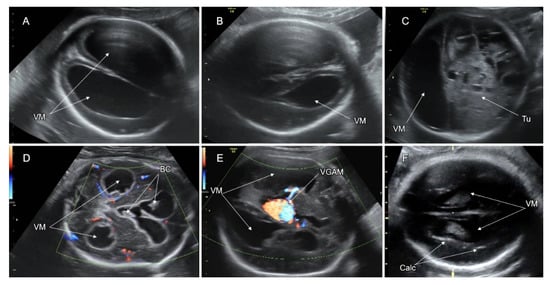

8. Ventriculomegaly